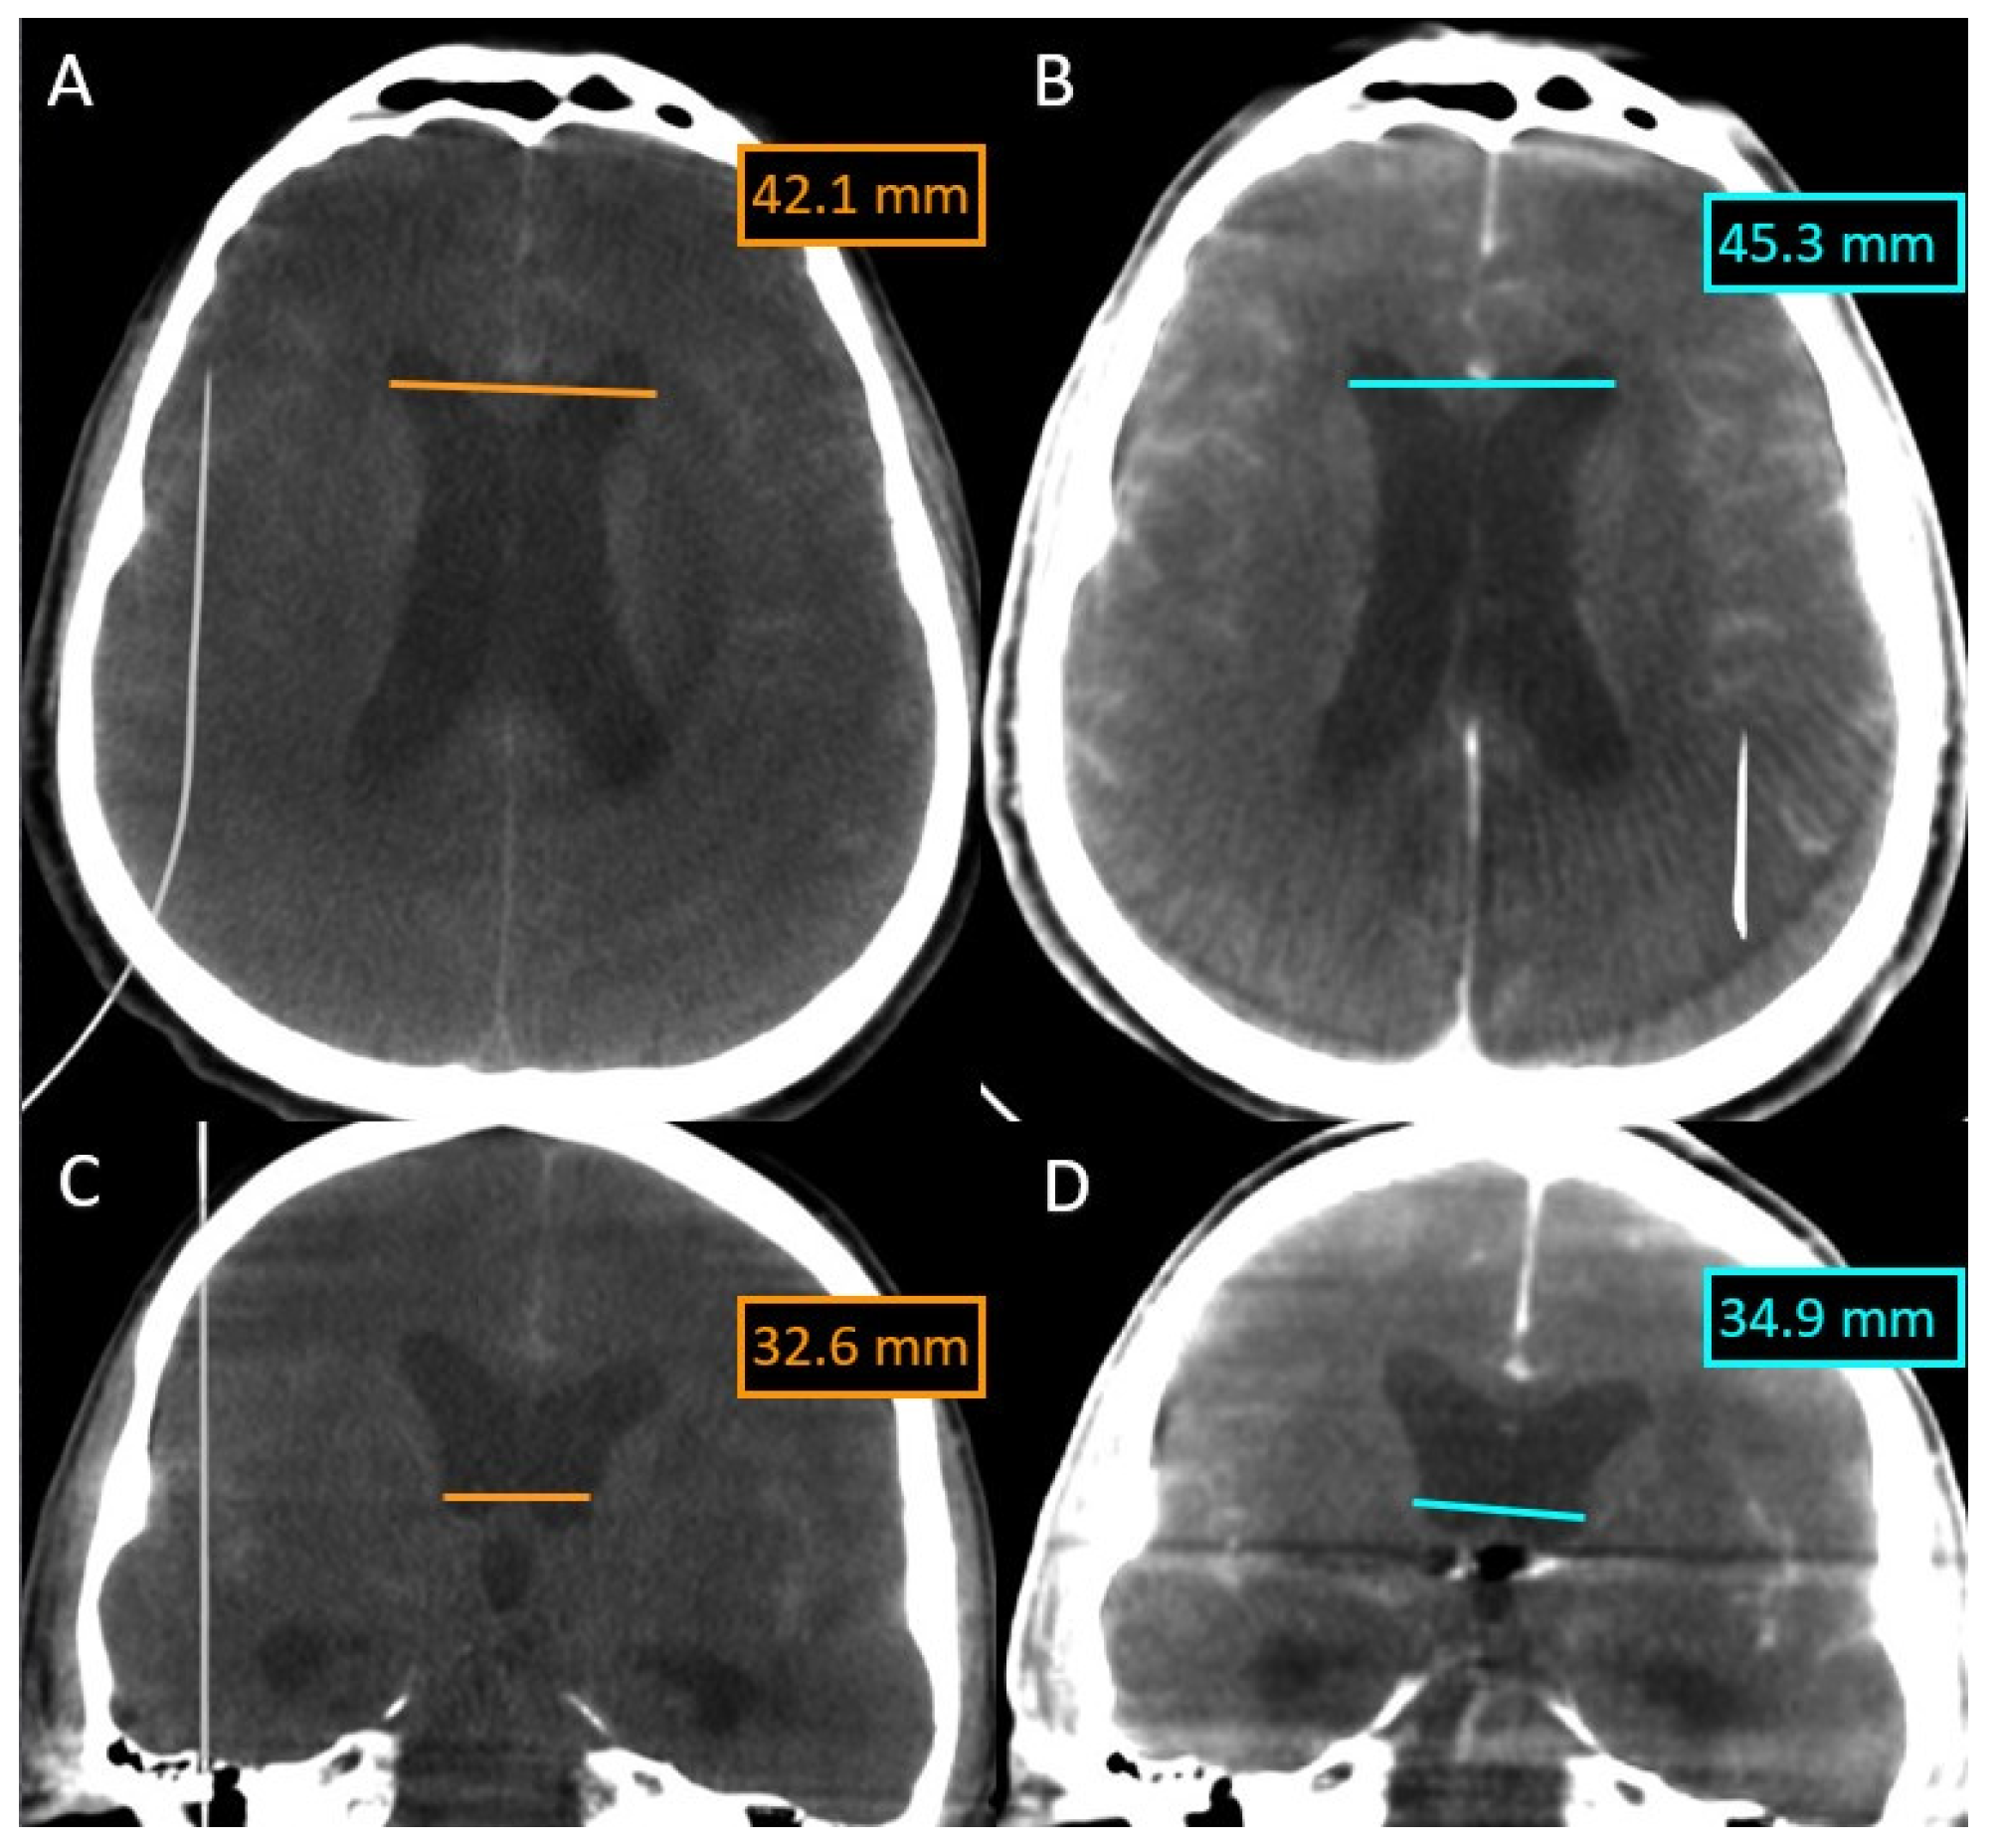

We present a 48-year-old patient with a subarachnoid hemorrhage Fisher IV through a rupture of the anterior communicating artery aneurysm. The aneurysm with a diameter of 4.9 × 5.2 mm, a height of 5 mm, and a neck of 4.2 mm was treated with a balloon-assisted coil embolization (Figure 4).

Figure 4.

(A,B) Anterior communicating artery (ACoA) aneurysm size—right internal carotid artery 3DRA volume. (C,D) DSA images ACoA aneurysm balloon-assisted coil embolization (red arrow—coils; yellow arrow—balloon), placed in contralateral A2 segment.

In this case, we overlaid two XperCT volumes (pre-operative and post-operative) to assess the evolution of hydrocephalus (Figure 5). We noticed that there is a difference of 2–3 mm between the size of the ventricles at the beginning and at the end of the intervention for the embolization of the aneurysm of the anterior communicating artery, a difference that appeared in 90 min.

Figure 5.

Evolution of hydrocephalus—comparison with the Overlay software. (A) XperCT volume axial preoperative. (B) XperCT volume axial postoperative. (C) XperCT volume coronal preoperative. (D) XperCT volume coronal post-operative.

The overlying was performed automatically and quickly, as we were dealing with volumes with numerous bone landmarks. No intraoperative bleeding was detected, either, and the hyperdense appearance at the end of the intervention was due to the contrast media.